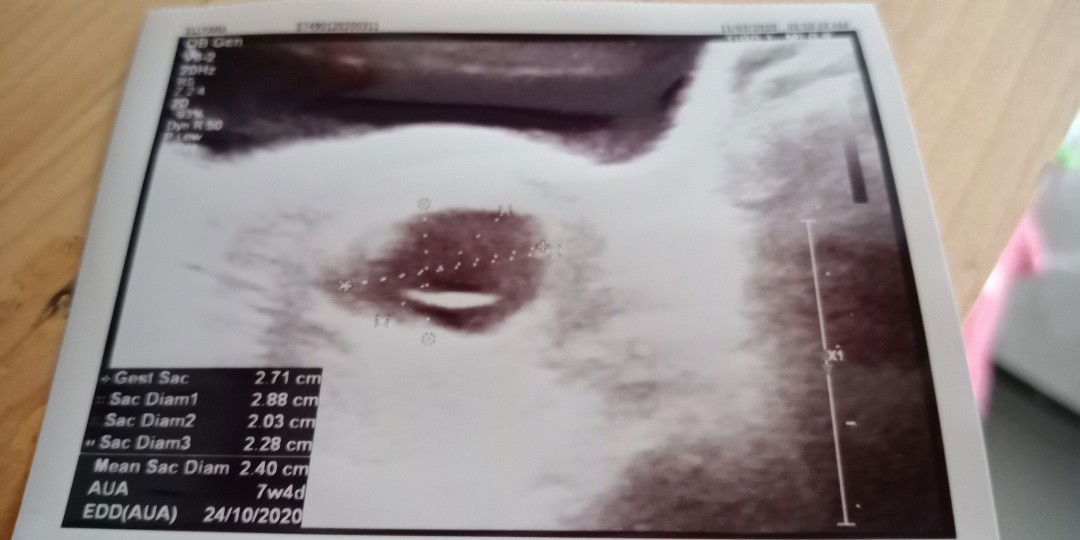

UK 12w tapi hasil USG 7w vonis BO

Bun.. Kemarin aku USG ke dokter. UK harusnya 12w tapi setelah USG cuma kantong doang yang ada, dan UK di usg menjadi 7w Vonis BO. 2minggu lagi disuruh balik lagi. Kalau masih kosong di suruh kuret. Apa yang salah dari aku ya?? Sedih rasanya :( Ada yang pernah ngalamin nggak bun? Atau ada saran apa gitu?